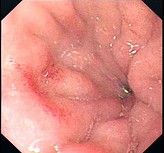

女性,28岁。间断性上腹隐痛不适1月余。发育正常,营养中等,表情自然,皮肤无黄染,腹平坦,腹肌软,全腹无压痛反跳痛,肝脾肋缘下未触及,胃镜检查如下图,诊断()。

A:十二指肠血管畸形

B:十二指肠溃疡并出血

C:十二指肠球部息肉

D:十二指肠球炎

E:十二指肠克罗恩病

第3题,共4个问题

(单选题)肠镜检查如图,最可能的诊断是()。

A:溃疡性结肠炎

B:肠恶性淋巴瘤

C:结肠癌

D:Crohn病

E:结肠多发性息肉